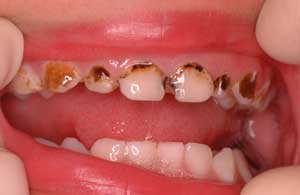

| 子どもの前歯でも |

進行止めのためのサホライドを塗ると

こんな風に黒くなります。

ごく表面の虫歯は茶色くなります。

穴は開いたままです。 |

虫歯部分を取り除き、レジンで治すと

きれいになります。

ラバーダム下なら安全で確実にできます。

3歳でも、前歯がきれいな方が私は好きです。 |